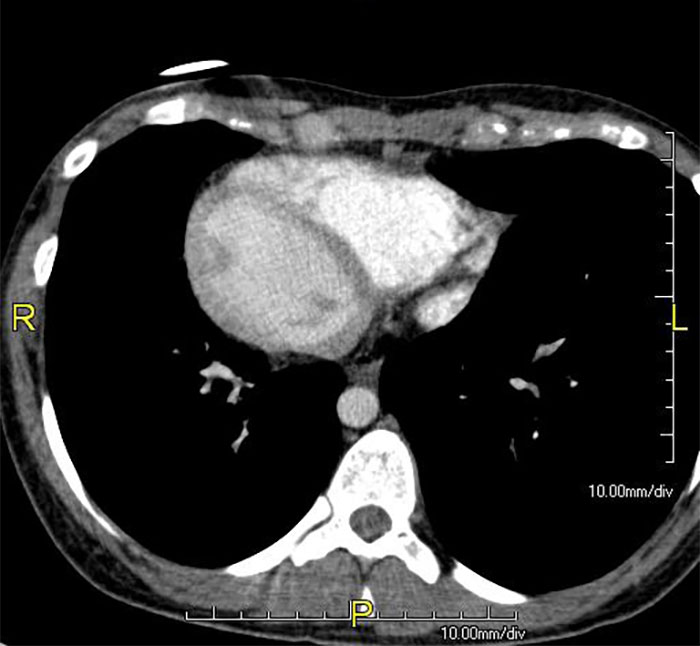

Hace unos 30 años, una mujer bebió desatascador de tuberías para suicidarse tras la muerte de su madre. Sobrevivió.

Pero se destruyó por dentro. Al final, se le conectaron los intestinos al esófago porque le extirparon el estómago por el daño excesivo.